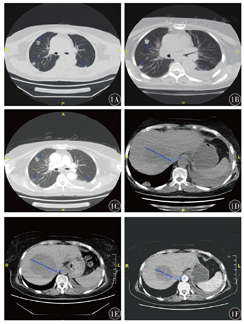

患者,女性,63岁,2016年9月开始出现进食后哽噎,胃镜检查结果示上胸段食管癌,活组织病理检查提示鳞状细胞癌。PET-CT扫描提示食管癌伴左锁骨上和纵隔淋巴结转移。在征得患者同意后,对患者进行了同步放化疗。患者接受食管和相关淋巴结区域病变的放疗,同时每周接受紫杉醇(50 mg/m2)和卡铂(AUC2)的联合化疗方案,共6个周期。6个月后,CT扫描显示腹膜后淋巴结转移。采用立体定向放射疗法(SBRT)治疗局部病变。但3个月后,患者食管处病变复发,并发生多处肺转移。患者接受mFOLFOX6方案姑息化疗:奥沙利铂85 mg/m2,第1天;亚叶酸钙400 mg/m2,第1天;5-氟尿嘧啶400 mg/m2,第1天;5-氟尿嘧啶2 400 mg/m2,持续静脉注射,共5个周期。CT复查显示疾病进展(PD),伴有胸闷、气促的症状,同时在肝脏中发现了新的病变。采用免疫组织化学法检测程序性死亡受体配体1(PD-L1)和DNA错配修复(MMR)状态,结果显示PD-L1阴性表达,MMR正常。在获得患者的知情同意后,从2018年6月6日开始,采用派姆单抗(200 mg,第1天,3周1次)联合安罗替尼(12 mg,第1天至第4天,3周1次)治疗。2周后,患者气促和胸闷的症状得到缓解。治疗1个月后胸部CT示:一些肺结节的体积变小,胸腔积液量减少;肝转移灶在1个月内增大,但在2个月的治疗后体积明显减小(图1)。患者接受联合治疗7个月后,定期评估显示病情稳定(SD)。2019年3月再次出现PD,并出现黄疸。2019年5月2日患者死于肝衰竭。